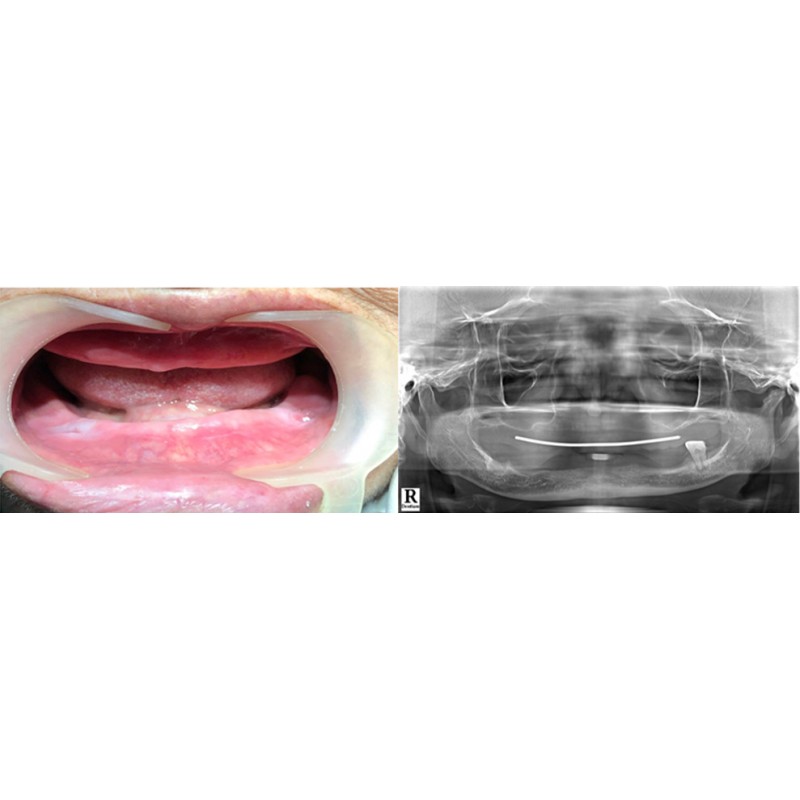

• Cấy ghép Implant

Bác sĩ Nguyễn Văn Hoàng Minh là người sáng lập ra Nha khoa Minh Nguyên. Là thành viên hiệp hội Implant thế giới ICOI (International Congress of Oral Implantologists thành lập từ năm 1972 tại Hoa Kì), Bác sĩ Nguyễn Văn Hoàng Minh đã tu nghiệp các nước Mỹ, Pháp, Đức,Thụy Sĩ, Hàn Quốc… và có hơn 25 năm kinh nghiệm chuyên cấy ghép Implant và chỉnh hình răng thẩm mỹ.